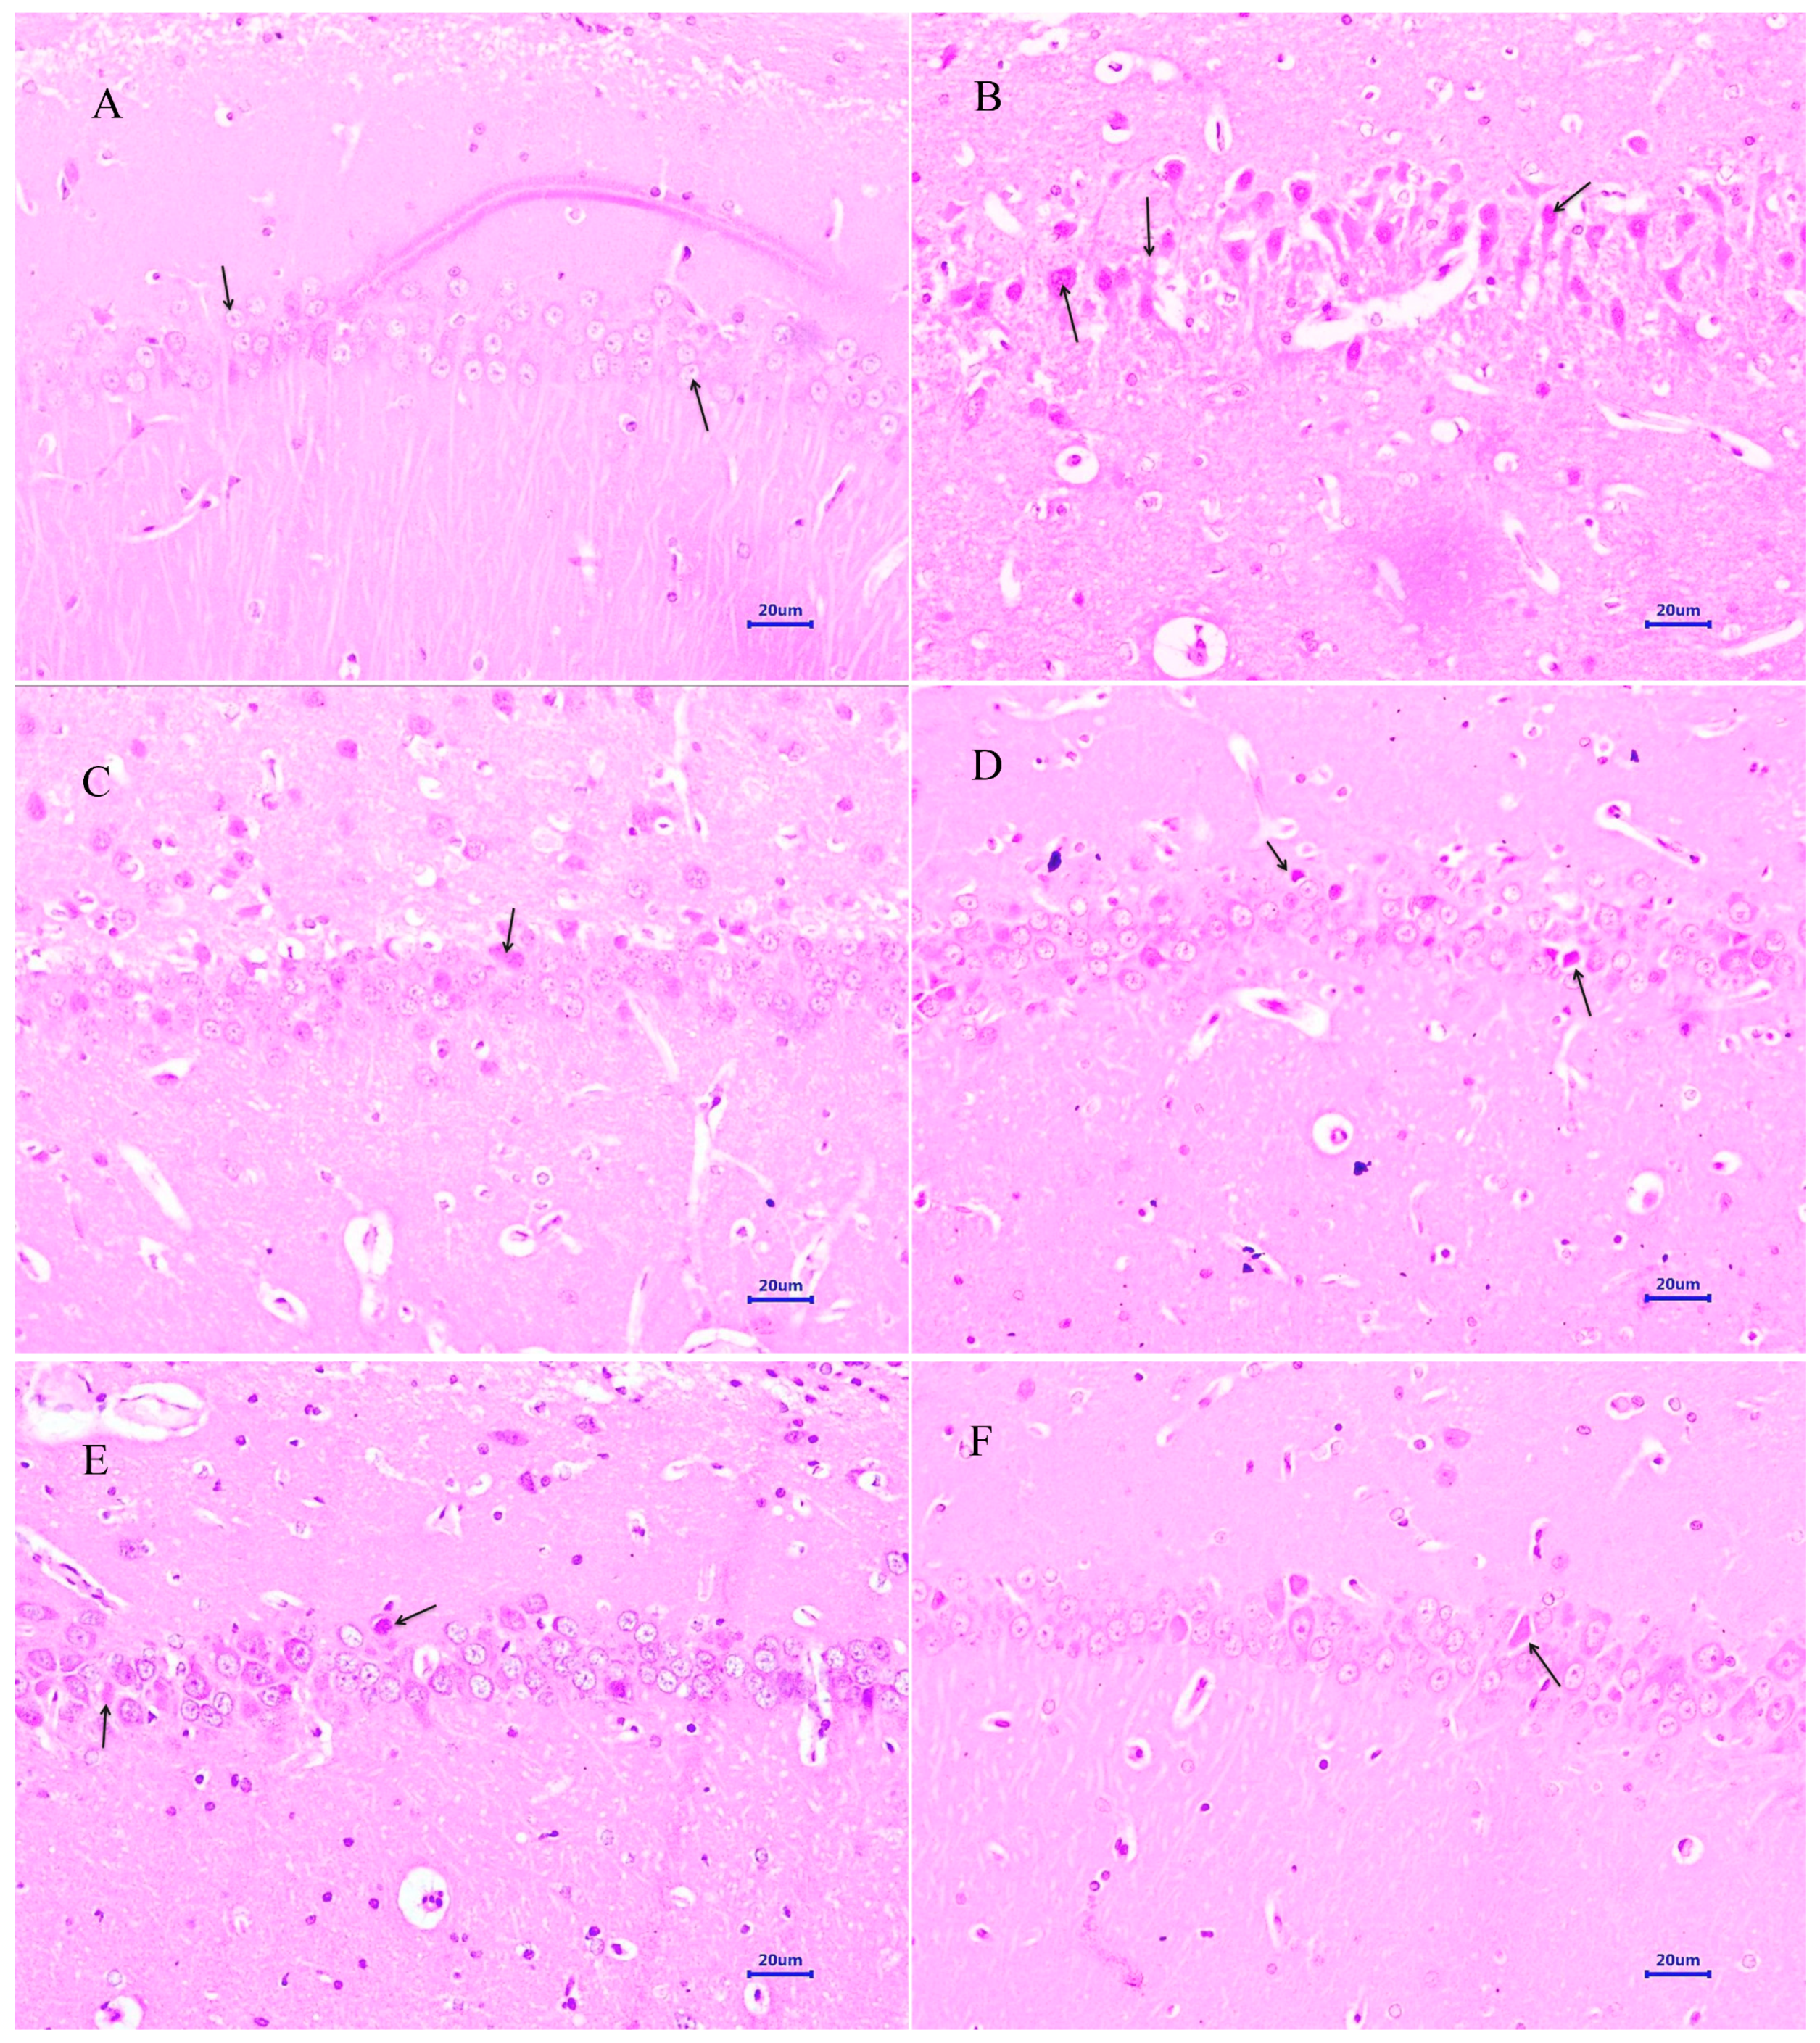

3.4.1. Haematoxylin and Eosin Staining

3.4.2. Congo Red Staining